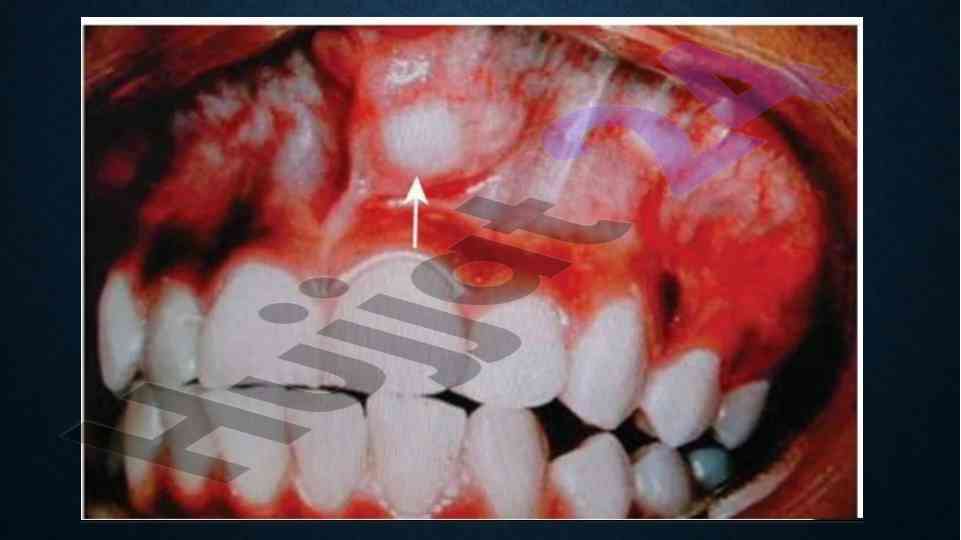

Maqola so'lak bezlari o'smalarining turli turlariga, klinik alg'oriyalarga va ularning davolash usullariga bag'ishlangan. Monomorf va polimorf adenoma haqida tafsilotlar keltirilgan.